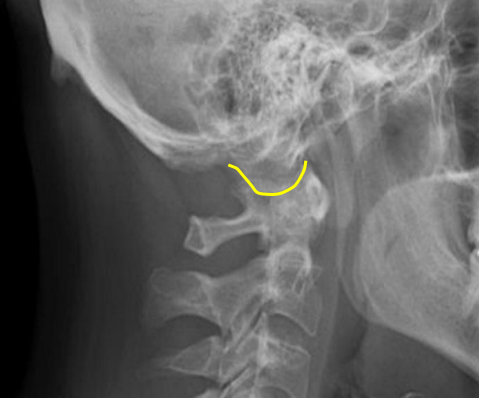

Occipital condyle

C1 anterior tubercle

C1 posterior arch

Odontoid process

Atlanto-Dental interspace

C1 lateral masses